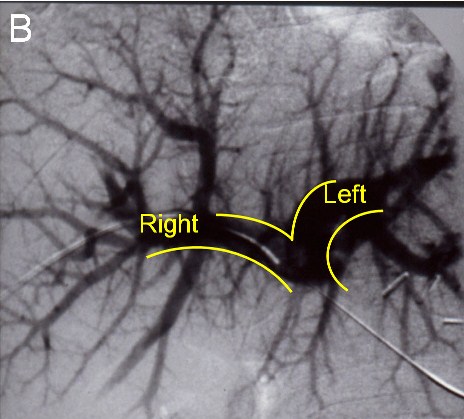

![]() |

| (B) Before the next operation, a portal vein embolization is done: Venogram showing a normal portal vein prior to embolization |